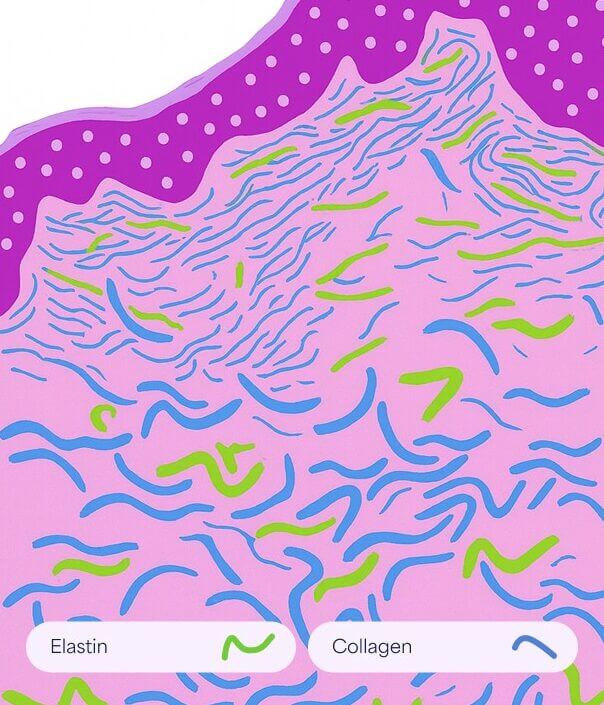

Dehnungsstreifen

Dehnungsstreifen

Normale Haut

Glatt und elastisch, wobei intakte Kollagen- und Elastinfasern für Festigkeit und Struktur sorgen.

Striae Rubrae

Glatt und elastisch, wobei intakte Kollagen- und Elastinfasern für Festigkeit und Struktur sorgen.

Striae Albae

Reife weiße Dehnungsstreifen, bei denen die Umstrukturierung des Kollagens zu einer Ausdünnung und einem Verlust der Pigmentierung führt.

So funktioniert es

- Fördert den Abbau von geschädigtem Kollagen

- Es induziert die Proliferation von Keratinozyten, die Wachstumsfaktoren freisetzen, um die Kollagenablagerung durch Fibroblasten und die Elastinablagerung zu fördern.

- Moduliert die Expression mehrerer Gene in der Haut (vaskulärer endothelialer Wachstumsfaktor, Fibroblasten-Wachstumsfaktor, epidermaler Wachstumsfaktor, Kollagen Typ I und III), die die Umgestaltung der extrazellulären Matrix fördern.